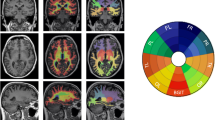

One significant (CBPT p value = 0.019) primary cluster emerged in the beta band (primary β, Fig. 1A and B), located on the right occipital region (detailed regions within the cluster are shown in Table 2). The correlation between the strength FC of this cluster and DR performance was negative, indicating that the higher the strength FC, the lower the memory performance. In addition, the correlation remained significant when looking at the MCI (rho = − 0.236; p = 0.011) and CI (rho = − 0.207; p < 0.001) groups separately (Fig. 1B). The strength FC value was found to be higher in the MCI patients than in the CI individuals, but the difference did not reach significance (ANCOVA with age and education as covariates, p value = 0.150, F value = 2.079; see Fig. 1B).

A In dark blue, marked as primary β, is displayed the brain region whose functional connectivity strength (strength FC) was found inversely correlated with delayed recall (DR). In light blue are depicted the region, marked as secondary β, whose FC with the primary β cluster was found to inversely correlate with DR. B Scatter plot shows the correlation between primary β cluster strength FC and DR computed with the whole sample (gray), MCI patients (red), and cognitively intact (CI) participants (green). Boxplot graphic shows the average strength FC of the primary β cluster for each group. C Scatter plot shows the correlation between primary β < – > secondary β FC and DR computed with the whole sample (gray), MCI patients (red), and cognitively intact (CI) participants (green). Boxplot graphic shows the average seed link FC of the secondary β cluster for each group. In boxplot graphics, vertical blue line indicates 95% confidence interval, whereas salmon boxes depict avg ± sd

When exploring the seed-based FC in the brain, using the primary β cluster as seed, we found one significant secondary cluster whose FC with the primary cluster showed to be negatively correlated with DR. The correlation between DR and the seed link FC remained significant when looking at the CI (rho = − 0.165; p = 0.008) and MCI (rho = − 0.312; p < 0.001) groups separately (Fig. 1A and C). However, the average seed link FC was significantly different between groups (ANCOVA with age and education as covariates, p value = 0.006, F value = 7.591), showing higher values for the MCI patients than for the CI individuals (Fig. 1C).

After we had described how lower levels of DR related to a distinctive strength FC profile, we analyzed the impact of APOE genotype as a moderator (W) between the pattern of FC in right occipital and left anterior areas in beta band (X) and the DR scores (Y) separately for each group. Our results showed a significant regression coefficient different from zero (b3 = − 1428.07, t (209) = − 3.10, p = 0.002) for XW only for the CI group, meaning that the effect of the network on episodic memory scores depends on the APOE genotype in cognitively intact participants. Once we defined the moderator effect of the APOE genotype, we tried to identify what was the threshold in FC that differentiated the episodic memory performance in carriers vs noncarriers. The Johnson-Neyman technique allowed the exact calculation of the conditions and the limit values in which a moderator obtains statistically significant slopes. Our results showed significant differences in FC values higher than 0.116, which means that the effect of APOE genotype on episodic memory scores was expressed only when the value of FC was above 0.116 (See Fig. 2).

Variation of the Spearman rho scores (age and education as covariates) for the correlation between delayed recall (DR) and secondary β seed link FC with ε4 APOE carriage. In order to show qualitatively the dependence of APOE in the relationship between DR and the FC of the link primary β <—> secondary β clusters, we have depicted the Spearman rho scores (computed with age as covariate) obtained for four groups: CI/MCI with and without any allele APOE 4. As it can be seen, the influence of the allele 4 of the APOE is notorious in the CI ε4 group. The solid black line that connects all groups is just indicative of the Rho’s variance